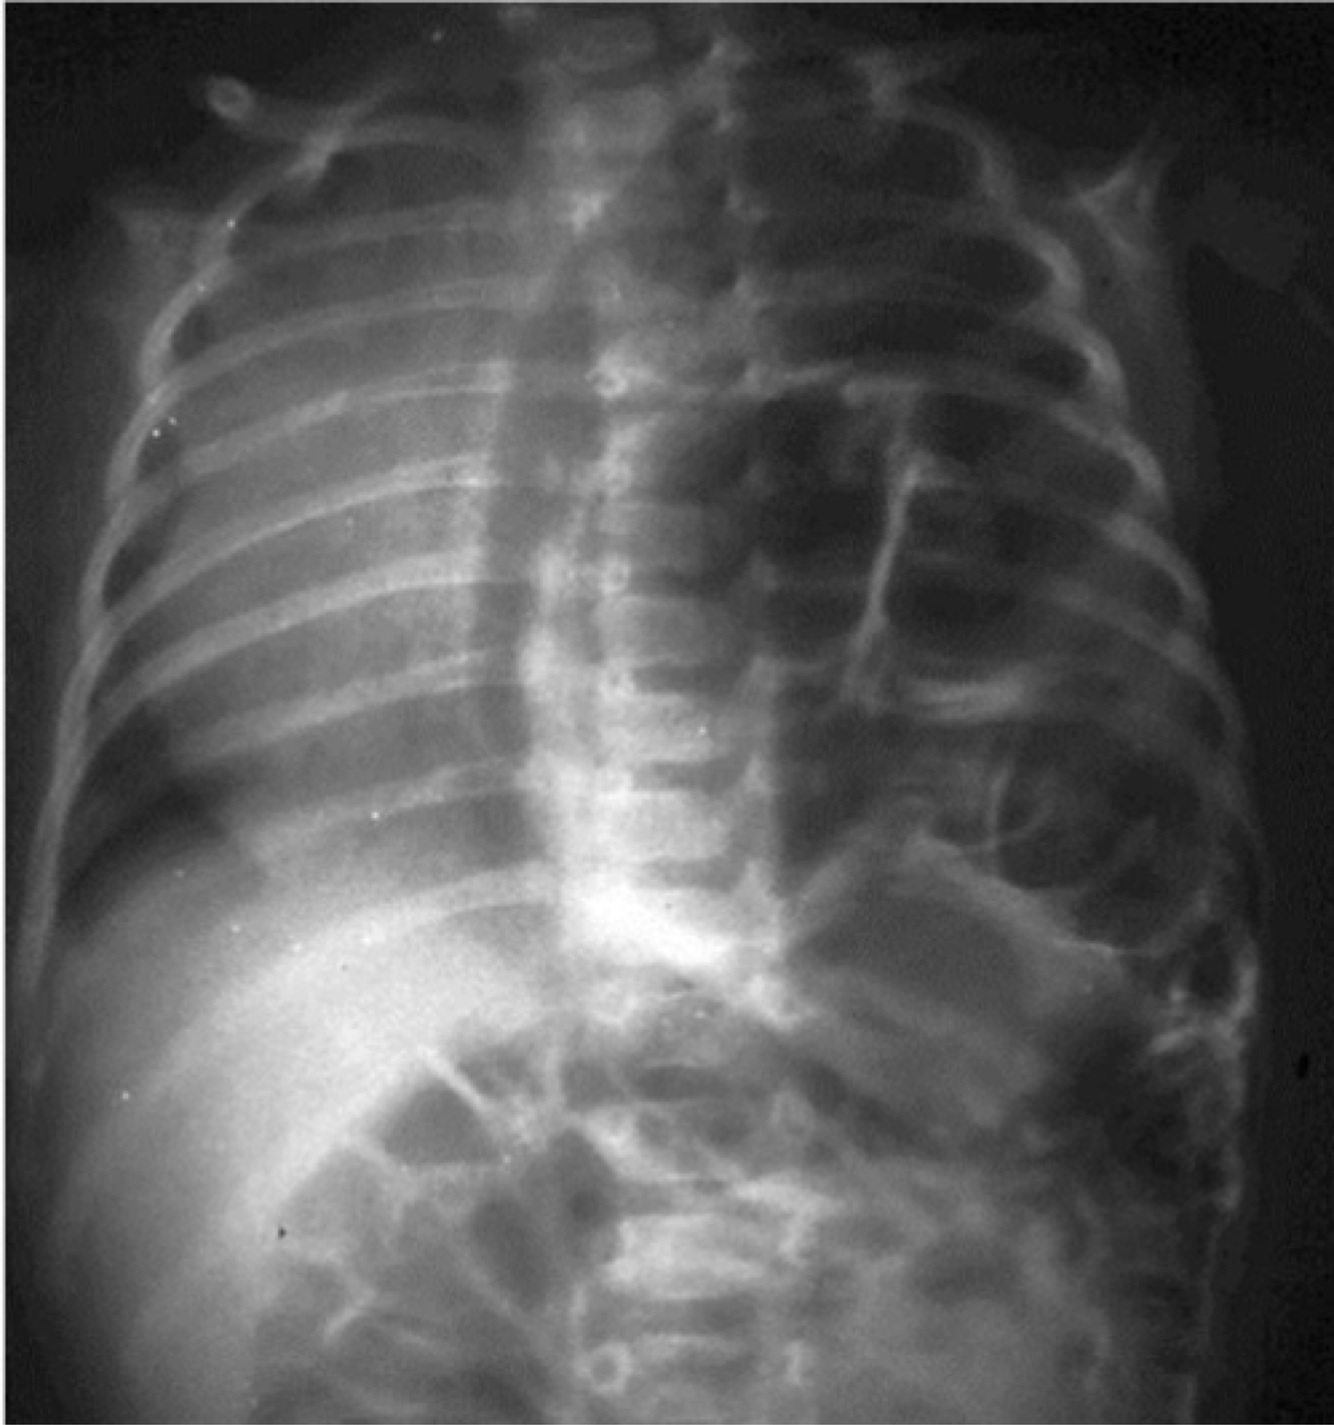

Tracheoesophageal fistula : distended gastric bubble and the nasogastric tube that has not reached the stomach but has rather coiled in the mediastinum